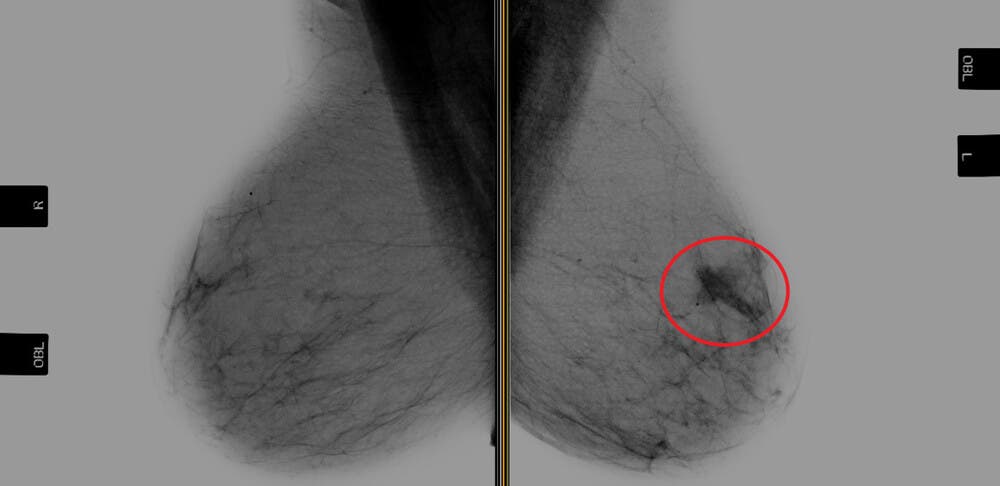

Bröstcancer inträffar när vävnaden i bröstet utvecklar elakartade tumörer. Denna sjukdom drabbar mest kvinnor, men kan även drabba män. Tusentals kvinnor dör av bröstcancer varje år. Detta eftersom den dessvärre upptäcks för sent i många fall . Här listar vi därför de främsta orsakerna till bröstcancer.